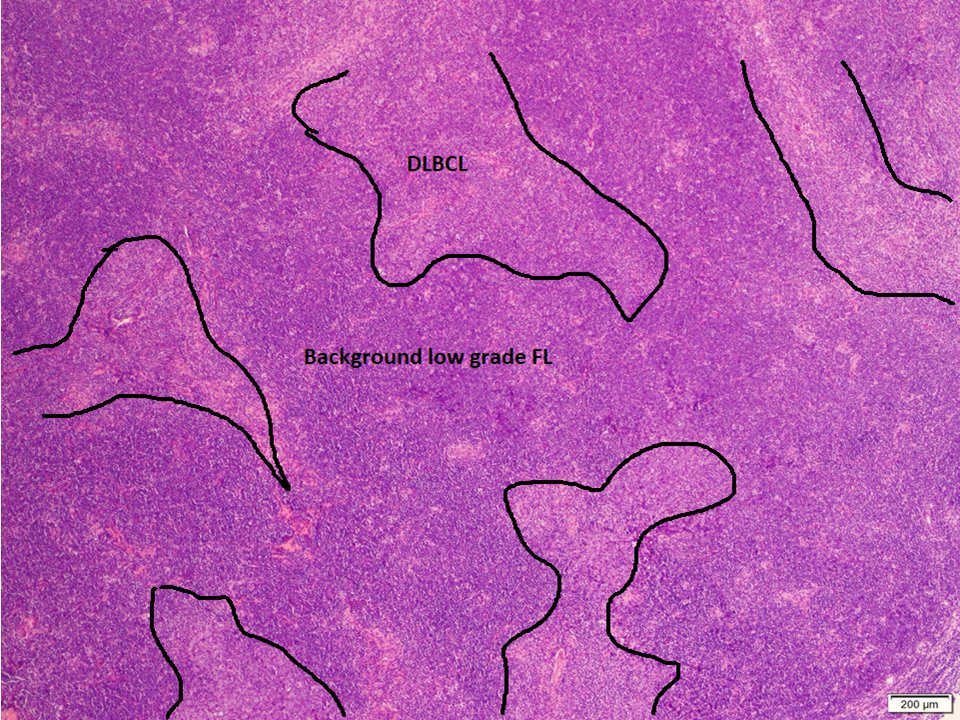

(1/3) Mutlifocal DLBCL arising in a background of low grade follicular lymphoma, with a peculiar architecture #hemepath #LJMFridayUnknowns #VirtualHemepathMDA #lymsm #endcancer